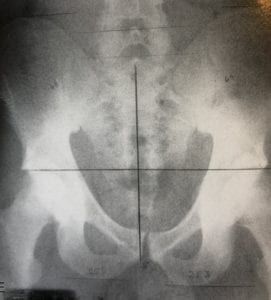

Illustration snedhet

Före och efter behandling (rtg-bilder hämtade från Plaugher/ Lopes Textbook of Clinical Chiropractic)

Asymmetri/ Symmetri